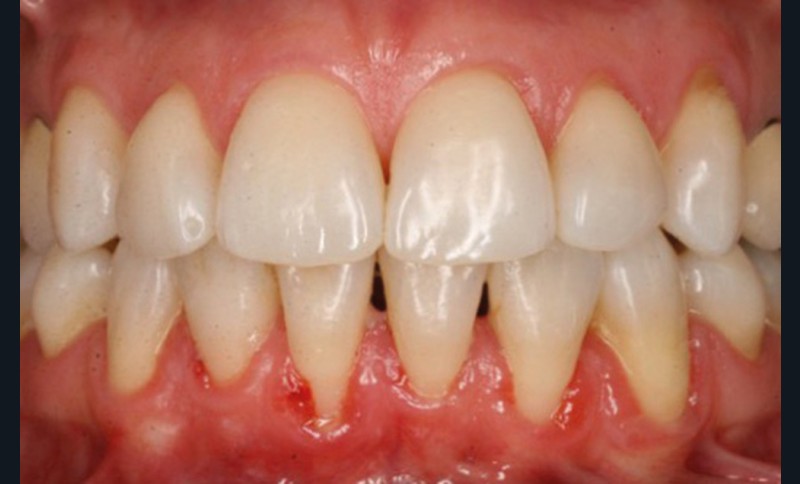

Quelle insatisfaction et quelle déception de constater, en cours ou à l’issue d’un traitement orthodontique, la fragilisation du parodonte, voire l’apparition d’une récession gingivale !

Le plan de traitement était-il le bon ? Fallait-il renforcer les tissus de soutien de la dent de manière préventive ?

C’est à ces questions que nous permettront de répondre les deux premiers conférenciers, parodontologistes : le Dr Béatrice Straub nous présentera le renfort parodontal minéralisé, technique qu’elle a développée et pratique depuis de nombreuses années, pour éviter les préjudices des mouvements orthodontiques à risque, notamment lors des décompensations préchirurgicales (fig. 1a-d) ; le Pr Anton Sculean abordera le thème des greffes, avec leurs indications, les différentes techniques à privilégier et illustrera ses propos par de nombreux cas cliniques aux résultats esthétiques impressionnants.

Le Pr Olivier Sorel insistera sur l’importance du respect des formes et des proportions anatomiques, pour éviter de voir apparaître, notamment chez les adultes, de très inesthétiques triangles noirs lors de la phase d’alignement (fig. 6a-b). Il présentera sa démarche diagnostique (évaluation de la forme des dents et de la dysharmonie dento-dentaire, fig. 7a-c) et l’intégration de la réduction amélaire proximale au plan de traitement, afin de s’assurer, en fin de traitement, la présence de papilles gingivales et donc d’un sourire harmonieux (fig. 8a-d).